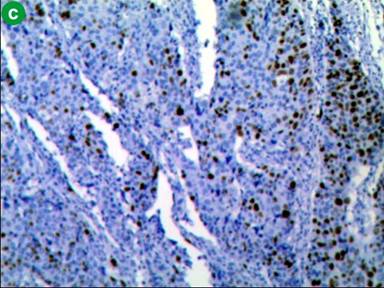

Patient underwent surgery, where a large mass of size 3 cm was found in the periampullary region with absence of body and tail of the pancreas confirming the diagnosis of agenesis of dorsal pancreas. A total pancreatectomy, duodenectomy, Roux-en-Y gastrojejunostomy, hepaticojejunostomy, and cholecystectomy were performed. On gross examination, a large ulceroinfiltrative lesion (3.0×2.5×2.0 cm) involving mostly periampullary region was found which was firm in consistency, pale greyish white in appearance with ill defined edges appearing to invade almost full thickness of the duodenal wall extending onto subserosa (Figure 3). Histopathological examination revealed invasive poorly differentiated adenocarcinoma with diffuse deep infiltration involving almost full thickness of the duodenal wall and invading subserosa (Figure 4a). Immunohistochemistry was done and the tumor cells were positive for immunohistochemical markers CA 19-9 (Figure 4b), cytokeratin-7, KI-67 (Figure 4c) and negative for CEA, cytokeratin-20. No lymph node metastasis was found.

Figure 4. a. Histopathological image of periampullary lesion (low power view) showing diffuse infiltration of tumor cells up to serosa off duodenum. b. Immunohistochemical staining of poorly differentiated tumor showing positive for tumor marker CA-19-9 and KI-67. c. Immunohistochemical staining of poorly differentiated tumor showing positivity for proliferative marker Ki-67. |

Our patient had periampullary carcinoma with agenesis of dorsal pancreas. Periampullary carcinoma is a tumor arising in the vicinity of the ampulla of Vater [17]. They can originate from the pancreas, duodenum and distal common bile duct [18]. These tumors are classified on the basis of their tissue of origin; they are different from the classical adenocarcinoma of the pancreas and they may be either benign or malignant tumors. Pathological examination of these tumors showed that 60% of are of pancreatic origin, 20% from ampulla of Vater, 20% from common bile duct and rest 10% arise from duodenum [18]. In literature around 9 cases pancreatic cancer have been reported in association with agenesis of dorsal pancreas. Among these pancreatic ductal adenocarcinoma was the most frequent, being reported in 5 patients, solid papillary tumor in 2 patients, IPMN with well differentiated, invasive mucinous adenocarcinoma in 1 patient and 1 patient with periampullary carcinoma [11, 19-23]. Only one case of periampullary carcinoma was reported by A Kapoor et al. [23] from India and ours is the second case. Our case had poorly differentiated adenocarcinoma and we did immunohistochemistry. Immunohistochemistry showed, tumor cells were positive for markers CA 19-9, KI-67, cytokeratin-7 (Figure 4b and 4c) and negative for intestinal markers like cytokeratin-20 and CEA (carcinoembryonic antigen) suggestive of pancreatico-biliary type of poorly differentiated adenocarcinoma. Pancreatico-biliary tumors follow a more aggressive course similar to that of pancreatic adenocarcinoma with worse prognosis. Our patient underwent total pancreatectomy and post operatively she developed insulin dependent diabetes mellitus.